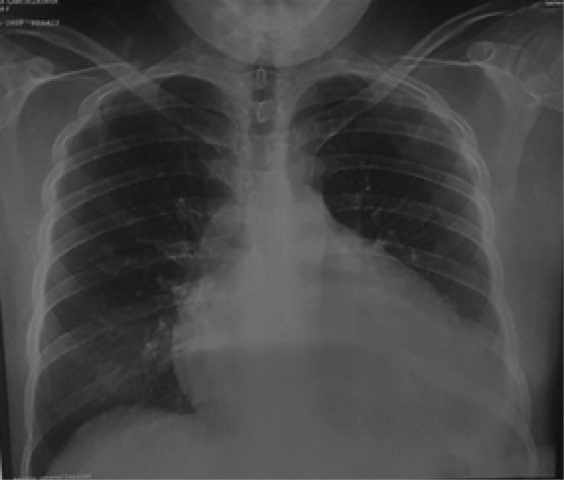

Radiografía de tórax (30/05/2020): se evidencia cardiomegalia III/IV con derrame pleural izquierdo. Partes óseas y blandas conservadas. Ver figura 1.

Radiografía de tórax: Cardiomegalia severa III/IV